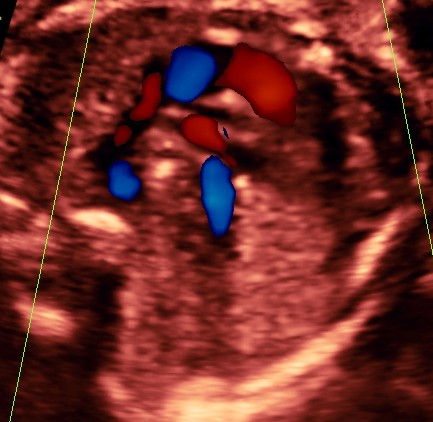

RV outflow tract with dilated Pulmonary trunk dividing into the Rt Pulm artery and the ductus seen. Aorta is not made out. ; SVC is seen